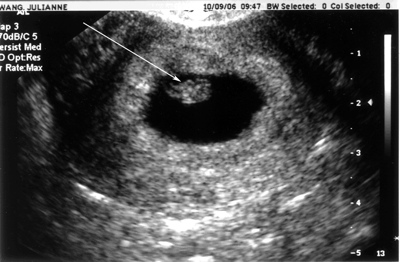

Ultrasound10-09-06

My First Ultrasound - Baby Wang is 1 cm long on Day 1 of Week 7 of gestation, Heartbeat is 143-147 bpm